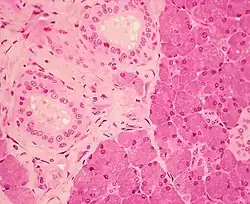

Histology

The gland has a capsule of its own of dense connective tissue but is also provided with a false capsule by the investing layer of the deep cervical fascia. The fascia at the imaginary line between the angle of the mandible and the mastoid process splits into a superficial and a deep lamina to enclose the gland. The risorius is a small muscle embedded with this capsule substance.

The gland has short, striated ducts and long, intercalated ducts.[10] The intercalated ducts are also numerous and lined with cuboidal epithelial cells and have lumina larger than those of the acini. The striated ducts are also numerous and consist of simple columnar epithelium, having striations that represent the infolded basal cell membranes and mitochondria.[8]: 273

Though the parotid gland is the largest, it provides only 25% of the total salivary volume. The serous cell predominates in the parotid, making the gland secrete a mainly serous secretory product.[10]